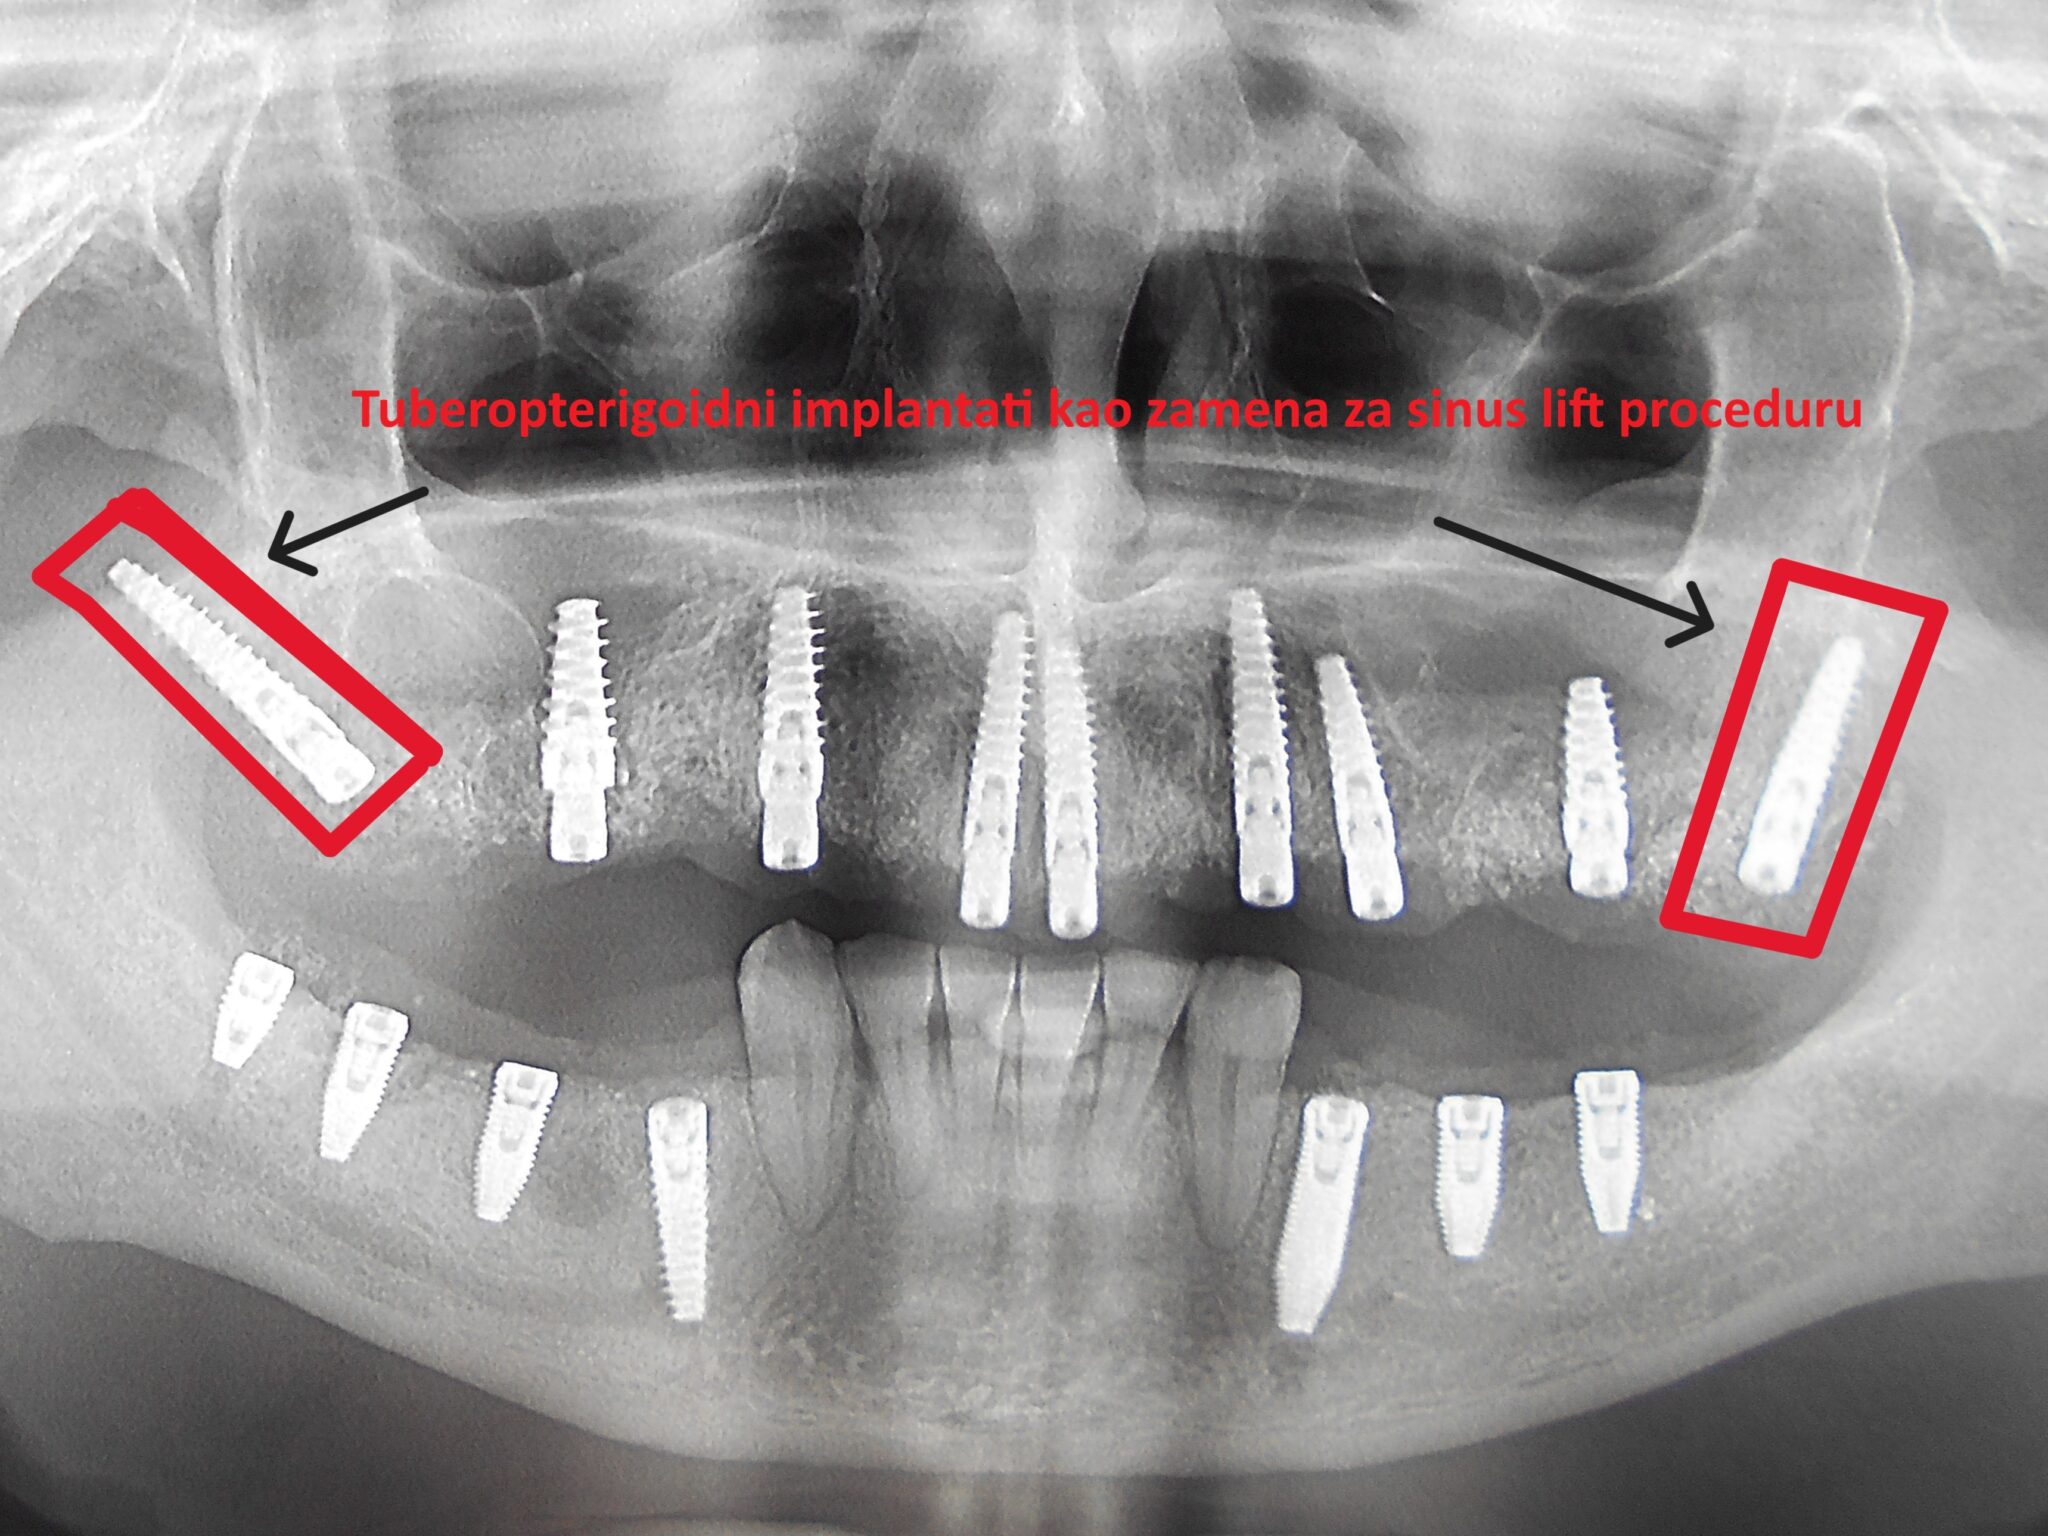

Na slikama su prikzani tubero-pterigoidni implantati postavljeni u cilju da se izbegne sinus lift procedura, čime je omogućena izrada fiksnog protetskog rada, sa kompletanim zubnim nizom, uz minimalnu površinu naleganja na meka tkiva.

Ovaj tip implantata omogućava izbegavanje sinus lift operacije, koja se inače koristi za povećanje koštane mase u predelu maksilarnog sinusa.

Operacija sinus lifta zahteva komplikovanu hiruršku proceduru, a dužina čekanja na definitivni protetski rad na implantatima u toj regiji traje i do dve godine. Ugradnja tuber-pterigoidnih implantata predstavlja relativno jednostavnu metodu, ali zahteva veliko iskustvo, preciznost i temeljno znanje iz anatomije i oralne hirurgije.

Tuber-pterigoidni implantat skraćuje vreme izrade definitivnog rada na implantatima i njime se izbegavaju neprijatnosti posthirurškog toka operacije sinus lifta.